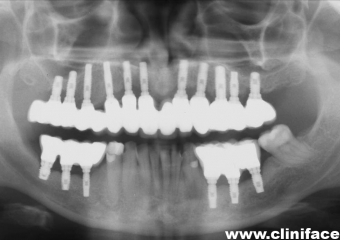

Raio X final